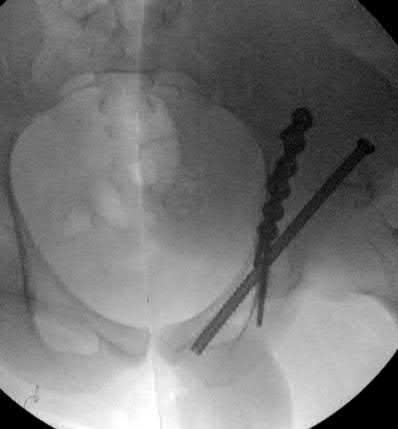

A 12-year-old obese boy presents with vague left thigh and knee pain. He is diagnosed with a Slipped Capital Femoral Epiphysis (SCFE) as seen in similar clinical scenarios. During percutaneous in-situ fixation, unrecognized penetration of the guide wire into the hip joint occurs. What is the most likely specific complication resulting from this technical error?

Correct Answer: Chondrolysis

Explanation:

Chondrolysis is a severe complication of SCFE characterized by rapid destruction of the articular cartilage. While it can occur idiopathically, its most established iatrogenic cause is unrecognized intra-articular hardware penetration. The 'approach-withdraw' fluoroscopic technique is required during pinning to assure pins are entirely intraosseous. Avascular necrosis (AVN) is usually due to damage to the epiphyseal blood supply (retinacular vessels) secondary to the initial displacement, forceful closed reduction, or posterosuperior pin placement.